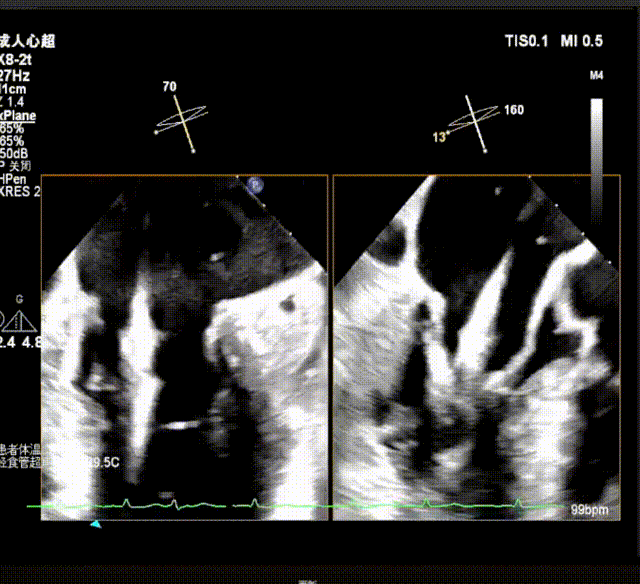

关闭瓣膜夹在超声指引下推进到左心室;打开瓣膜夹至120°,超声下抓捕瓣叶

确定瓣膜夹与病变区域垂直后,放下夹片,超声确认前叶后叶都夹合充分,3D检查瓣膜夹位置.

前瓣超声测量抓取1.00cm,后瓣抓捕1.04cm,抓捕充分;

瓣膜夹释放前评估发现返流改善明显,仅存少量返流。